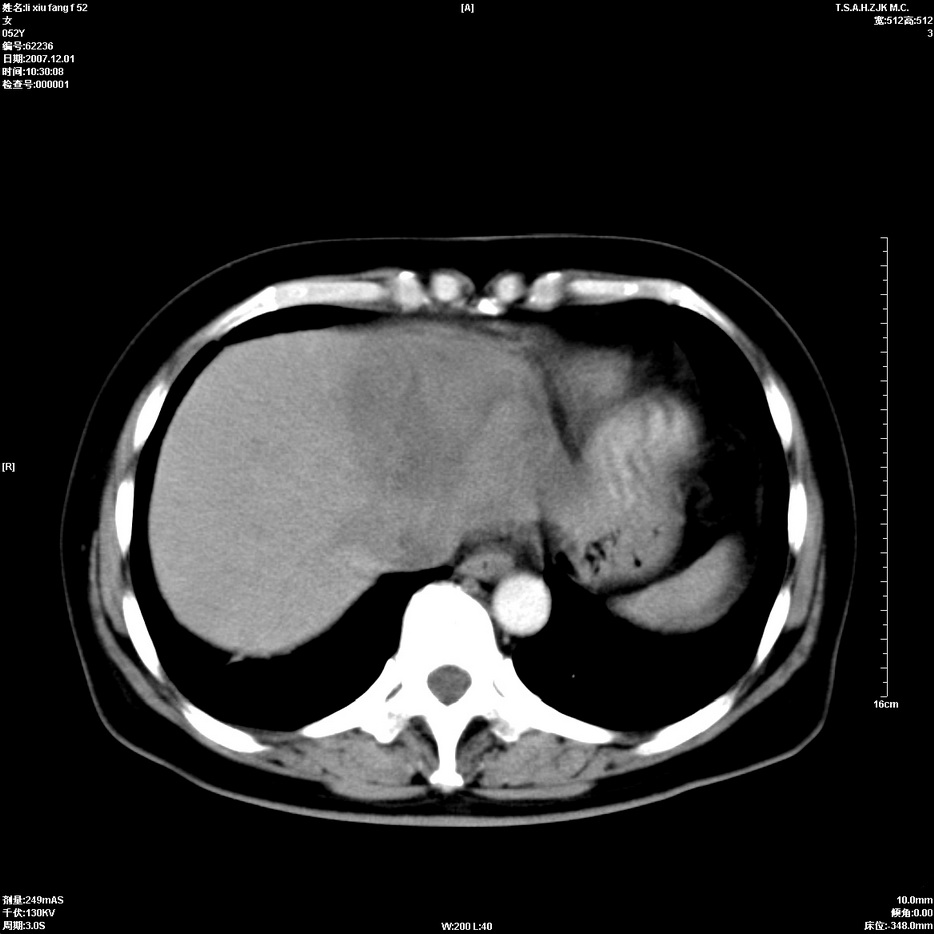

标题: CT12858:女,52岁,胎甲球蛋白861肝左叶占位,肝癌。下腔静 [打印本页]

标题: CT12858:女,52岁,胎甲球蛋白861肝左叶占位,肝癌。下腔静

肝左叶巨大低密度灶肿块,增强符合快进快出表现,有动静脉交通支;静脉期,下腔静脉内有充盈缺损,afp明显升高,支持肝癌并下腔静脉癌栓形成。

以下是引用拾荒者在2008-4-15 22:57:00的发言:[br]肝左叶巨大低密度灶肿块,增强符合快进快出表现,有动静脉交通支;静脉期,下腔静脉内有充盈缺损,afp明显升高,支持肝癌并下腔静脉癌栓形成。